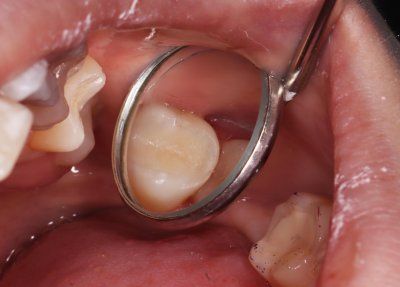

Клинический случай: зуб 26, средний кариес. На зубе 26 на жевательной, медиальной поверхности дефект твердых тканей.

Реставрация – OptiBond Solo Plus, материал - Filtek Z-250 A2.